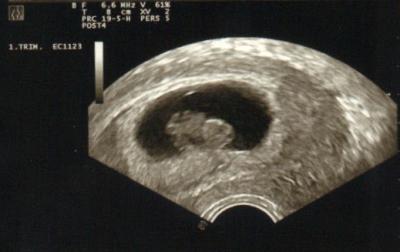

Außerdem wurde gestern wieder fleißig geschallt.

Den Kopf, die Füße und den Rücken konnte man prima erkennen, aber das kleine weiß schon genau wie man sich gut versteckt, denn anfangs war nur der große Kopf zu sehen.

Das Herzchen schlägt in einem guten Takt, die Füßchen bewegen sich und auch ansonsten ist alles in Ordnung.

SSL (Scheitel-Steiß-Länge) sind schon 22mm.

Hier ein Suchbild...